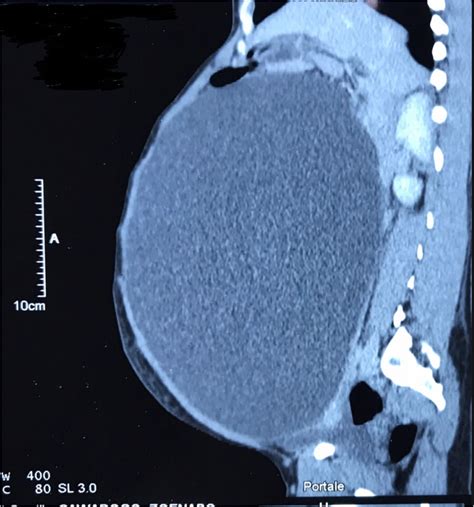

- Cyst size: Cysts larger than 5–10 centimeters are generally monitored more closely due to increased risk of complications such as ovarian torsion (twisting of the ovary) or rupture.

- Symptoms: Large cysts often cause noticeable symptoms—pelvic pain, bloating, early satiety, or frequent urination—that may indicate a problem needing medical attention.